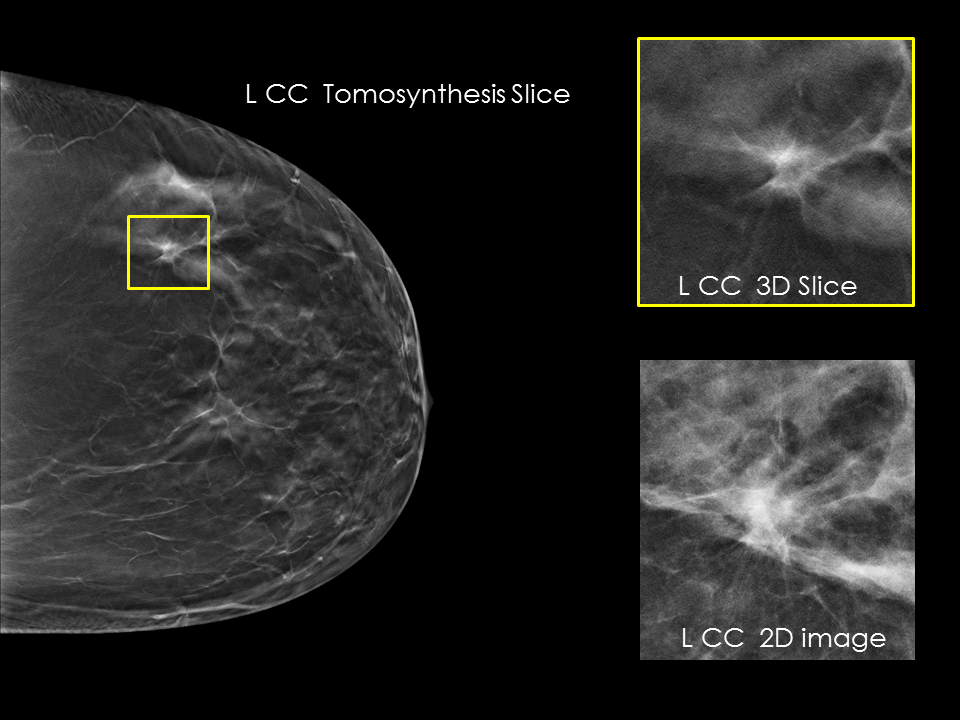

Better visibility

Designed to improve visibility of fine details for greater diagnostic confidence.*